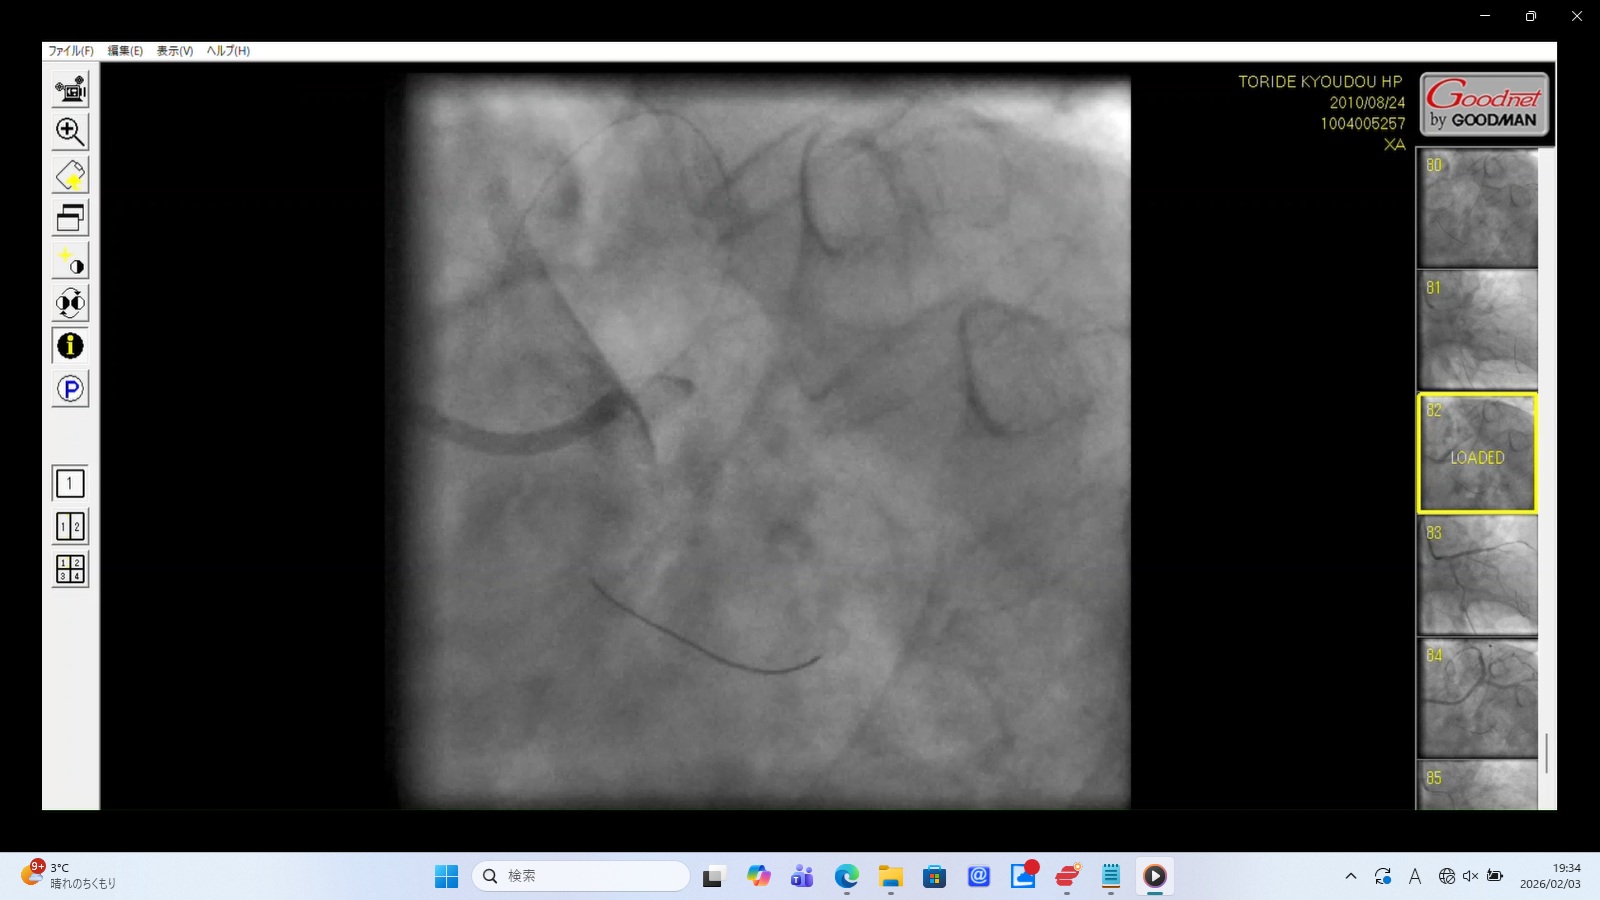

Caption: Iatrogenic Total Occlusion of the Left Main Trunk (LMT)

Medical Findings

Contrast Reflux: Upon injection, the contrast media fails to enter the coronary ostium and instead "bounces back" into the aortic root.

Suspected Dissection: The abrupt cessation of flow at the ostium suggests an iatrogenic dissection or mechanical collapse of the LMT.

Significance: This cuts off blood supply to approximately 75% of the myocardium. This is a periprocedural "Death Sentence" unless immediately bypassed.